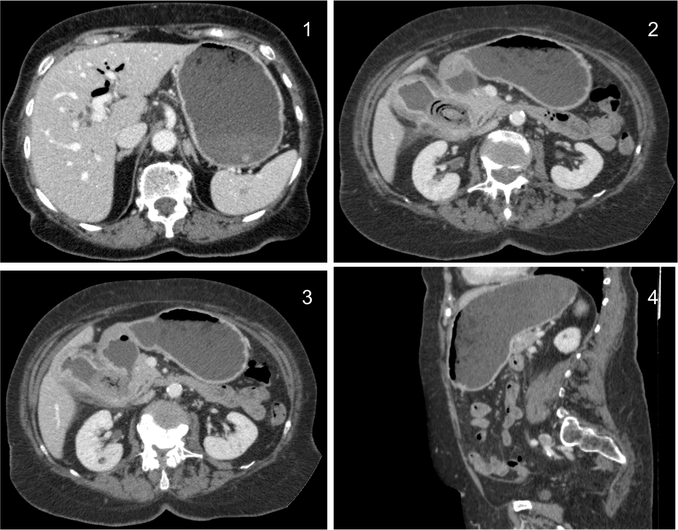

Lipoma intestinal: frecuente como punto guía o cabeza de invaginación en el instestino delgado. Aquí presentamos un caso de lipoma intraluminal en el colon, que producia obstrucción y cambios inflamatorios en el colon ascendente.